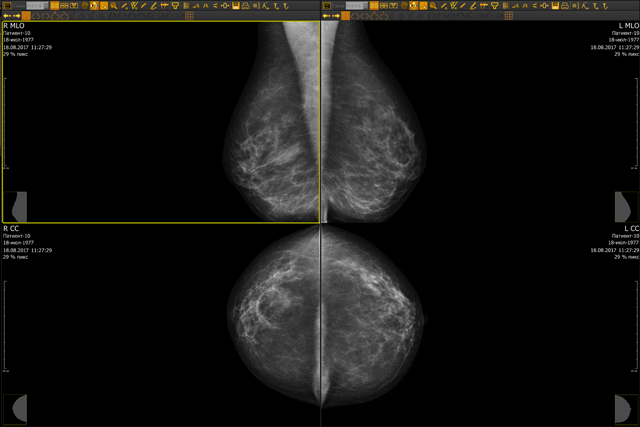

Маммографический аппарат «Маммо-4МТ» обеспечивает высококачественное рентгеновское изображение молочной железы, необходимое для точной диагностики и выявления ранних стадий рака.

Основными преимуществами маммографа являются простота эксплуатации и надежность, высокая разрешающая способность, низкая доза облучения пациента и персонала, режим автоматического выбора параметров экспозиции, высокое качество получаемых маммограмм.

Приемник обеспечивает высокую скорость получения качественных цифровых изображений. Технология непрямого преобразования рентгеновского излучения в электрический сигнал и специально разработанное программное обеспечение гарантируют стабильность работы и получение снимков высочайшего качества вне зависимости от температуры окружающей среды.

Компания рекомендует комплектовать маммограф автоматизированным рабочим местом рентгенолога (специализация: маммография), оснащенным двумя специализированными медицинскими высококонтрастными мониторами разрешением не менее 5 Мпикс, предоставляющим врачу полный набор необходимых инструментов для полноценного анализа диагностических снимков.